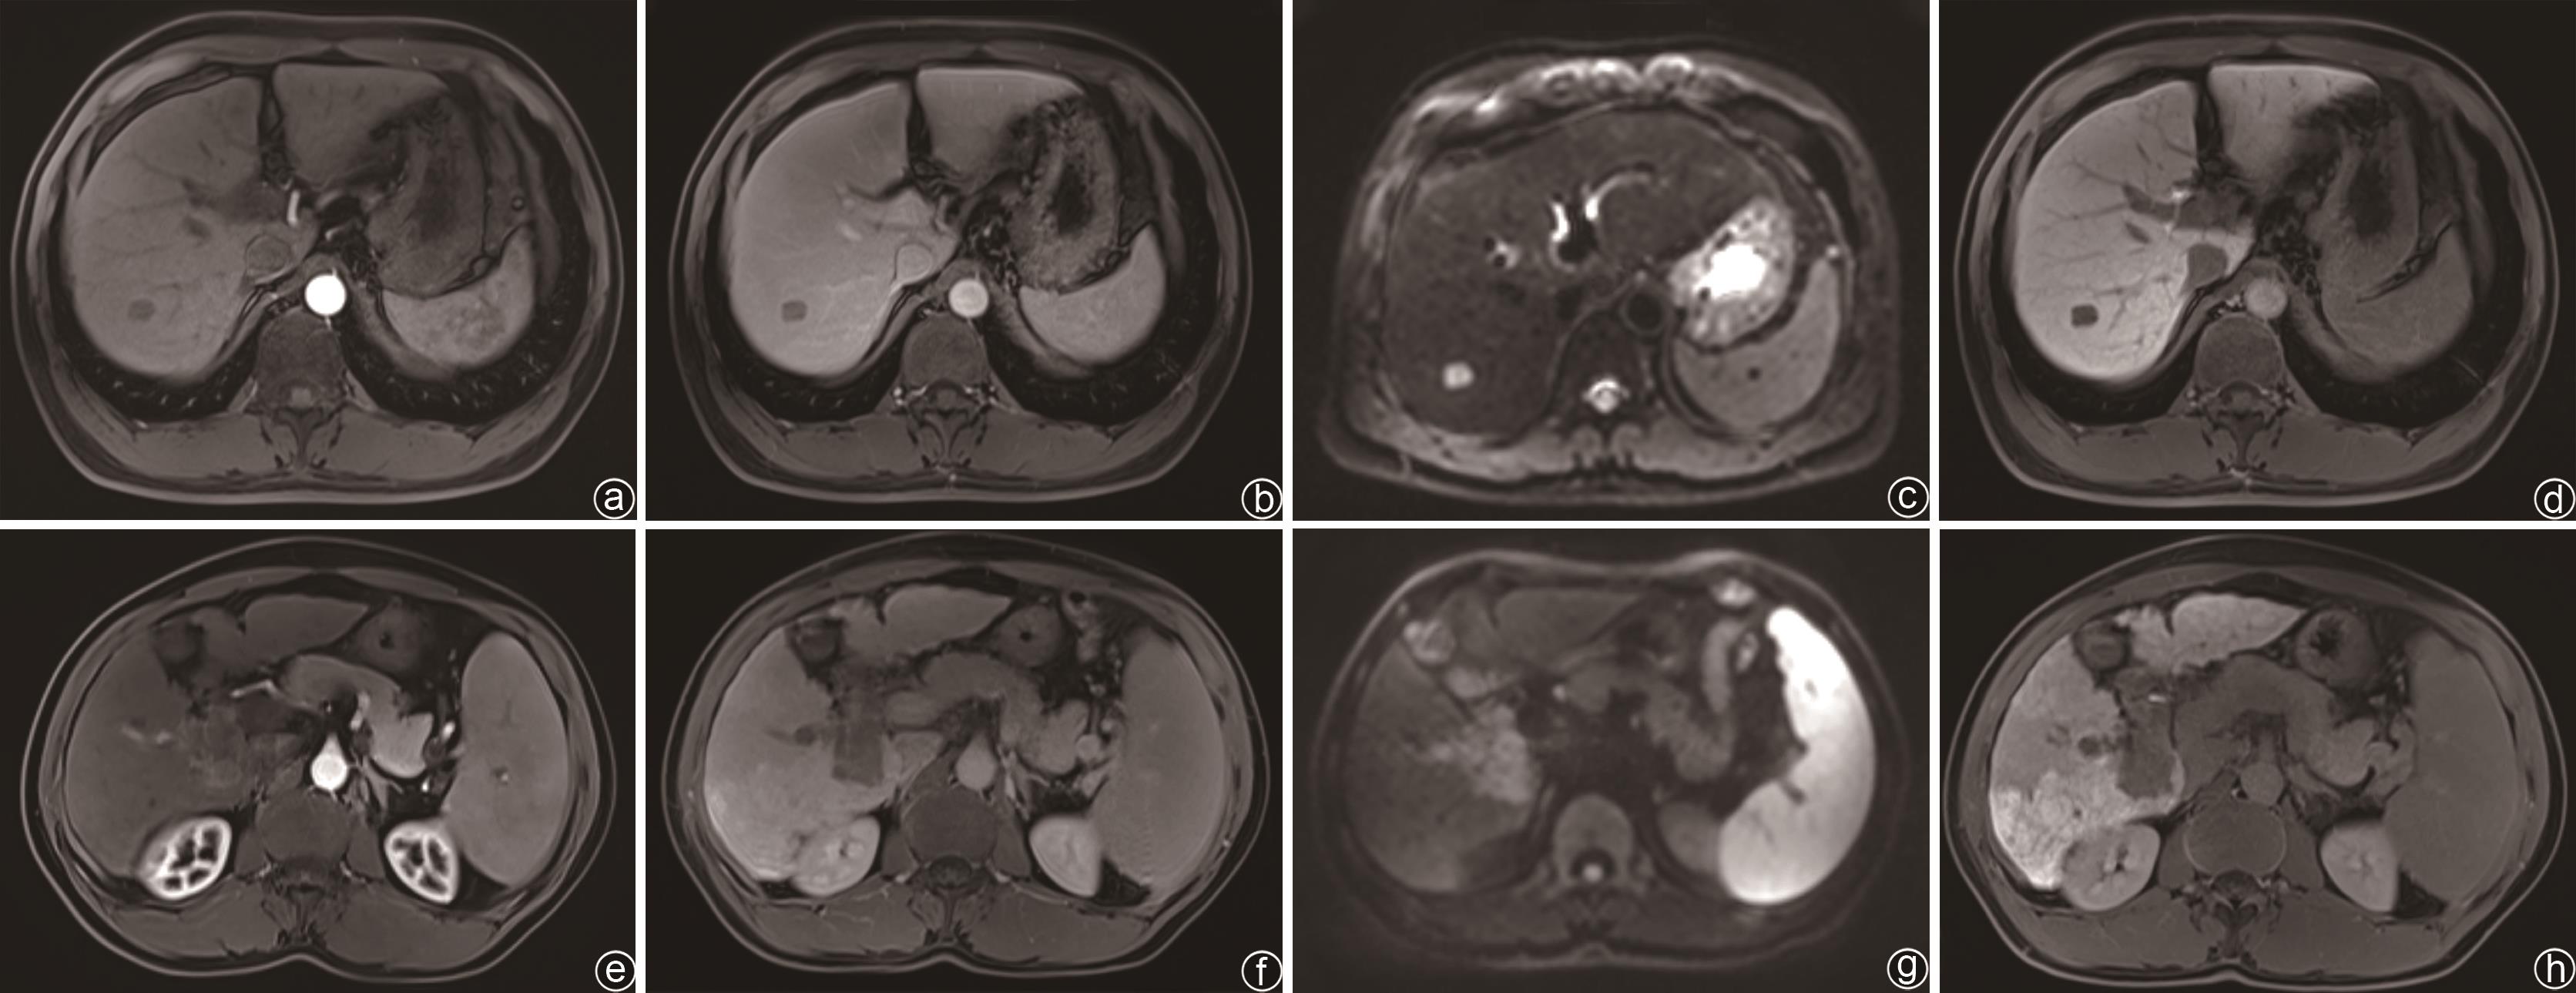

目的 探究临床指标联合MRI征象的列线图模型对原发性肝癌中医证型的判断效能。 方法 回顾性收集2018年9月—2023年7月在陕西中医药大学附属医院住院的138例原发性肝癌患者临床资料,并分为实证组(n=84)和虚证组(n=54),所有患者均在治疗前行钆塞酸二钠增强MRI扫描。计数资料组间比较采用χ2检验或Fisher确切概率检验。计量资料两组间比较采用成组t检验。应用Logistic回归分析原发性肝癌中医证型的独立预测因子,并构建列线图模型,将所有患者按8∶2随机分为训练组(n=110)和验证组(n=28)。通过校准曲线、受试者工作特征曲线(ROC曲线)和决策曲线评估模型的临床效能。 结果 实证组与虚证组比较,中性粒细胞、淋巴细胞、血小板、白蛋白、中性粒细胞/淋巴细胞比值、凝血酶原时间、甲胎蛋白、直接胆红素、间接胆红素、总胆红素、有无门静脉侵犯、肿瘤个数、肝胆期肿瘤信号和表观扩散系数差异均有统计学意义(P值均<0.05)。Logistic回归分析结果显示,甲胎蛋白(OR=0.003,95%CI:0.000~0.052,P<0.001)、凝血酶原时间(OR=0.032,95%CI:0.004~0.286,P=0.002)、淋巴细胞(OR=0.032,95%CI:0.004~0.268,P=0.002)、白蛋白(OR=0.009,95%CI:0.001~0.163,P=0.001)、中性粒细胞/淋巴细胞比值(OR=0.040,95%CI:0.003~0.457,P=0.010)、直接胆红素(OR=0.014,95%CI:0.001~0.198,P=0.002)、门静脉癌栓(OR=0.005,95%CI:0.000~0.115,P=0.001)、肿瘤个数(OR=12.740,95%CI:1.212~133.937,P=0.034)和表观扩散系数(OR=19.269,95%CI:3.163~117.387,P=0.001)是原发性肝癌中医证型分型的独立预测因子。训练组的ROC曲线下面积(AUC)、敏感度、特异度和准确度分别为0.962、84.1%、92.4%和89.1%,验证组的AUC、敏感度、特异度和准确度分别为0.848、63.6%、100.0%和85.7%。校准曲线显示列线图模型在训练组和验证组中的预测证型与实际证型之间有较好的一致性。决策曲线显示列线图在较大的阈值概率范围内有较好的净收益。 结论 基于临床指标联合MRI征象的列线图模型在判断原发性肝癌中医证型方面具有良好的临床效能和价值。 Abstract:Objective To investigate the performance of a nomogram model established based on clinical indices and magnetic resonance imaging (MRI) signs in determining the traditional Chinese medicine (TCM) syndrome types of primary liver cancer. Methods A retrospective analysis was performed for the clinical data of 138 patients with primary liver cancer who were hospitalized in The Affiliated Hospital of Shaanxi University of Chinese Medicine from September 2018 to July 2023, and the patients were divided into excess syndrome group with 84 patients and deficiency syndrome group with 54 patients. All patients underwent Gd-EOB-DTPA contrast-enhanced MRI scan before treatment. The independent-samples t test was used for comparison of continuous data between two groups, and the chi-square or the Fisher’s exact test was used for comparison of categorical data between groups. A Logistic regression analysis was used to investigate the independent predictive factors for the TCM syndrome type of primary liver cancer, and a nomogram model was established. The patients were randomly divided into training group with 110 patients and validation group with 28 patients at a ratio of 8∶2, and the calibration curve, the receiver operating characteristic (ROC) curve, and the decision curve were used to evaluate the clinical performance of this model. Results There were significant differences between the excess syndrome group and the deficiency syndrome group in neutrophils, lymphocyte count (LYM), platelet count, albumin (Alb), neutrophil-lymphocyte ratio (NLR), prothrombin time (PT), alpha-fetoprotein (AFP), direct bilirubin (DBil), indirect bilirubin, total bilirubin, presence or absence of portal vein invasion, number of tumors, hepatobiliary tumor signal, and apparent diffusion coefficient (ADC) (all P<0.05). The Logistic regression analysis showed that AFP (odds ratio [OR]=0.003, 95% confidence interval [CI]: 0.000 — 0.052, P<0.001), PT (OR=0.032, 95%CI: 0.004 — 0.286, P=0.002), LYM (OR=0.032, 95%CI: 0.004 — 0.286, P=0.002), Alb (OR=0.009, 95%CI: 0.001 — 0.163, P=0.001), NLR (OR=0.040, 95%CI: 0.003 — 0.457, P=0.010), DBil (OR=0.014, 95%CI: 0.001 — 0.198, P=0.002), portal vein cancer thrombus (OR=0.005, 95%CI: 0.000 — 0.115, P=0.001), number of tumors (OR=12.740, 95%CI: 1.212 — 133.937, P=0.034), and ADC (OR=19.269, 95%CI: 3.163 — 117.387, P=0.001) were independent predictive factors for TCM syndrome types of primary liver cancer. In the training group, the model had an area under the ROC curve (AUC) of 0.962, a sensitivity of 84.1%, a specificity of 92.4%, and an accuracy of 89.1%, and in the validation group, the model had an AUC of 0.848, a sensitivity of 63.6%, a specificity of 100.0%, and an accuracy of 85.7%. The calibration curve showed that the nomogram model had good consistency between predicted syndrome types and actual syndrome types in the training group and the validation group, and the decision curve showed that the nomogram model had good net benefits within a relatively wide range of threshold probability. Conclusion The nomogram model based on clinical indices and MRI signs has good clinical efficacy and value in judging the TCM syndrome type of primary liver cancer. -